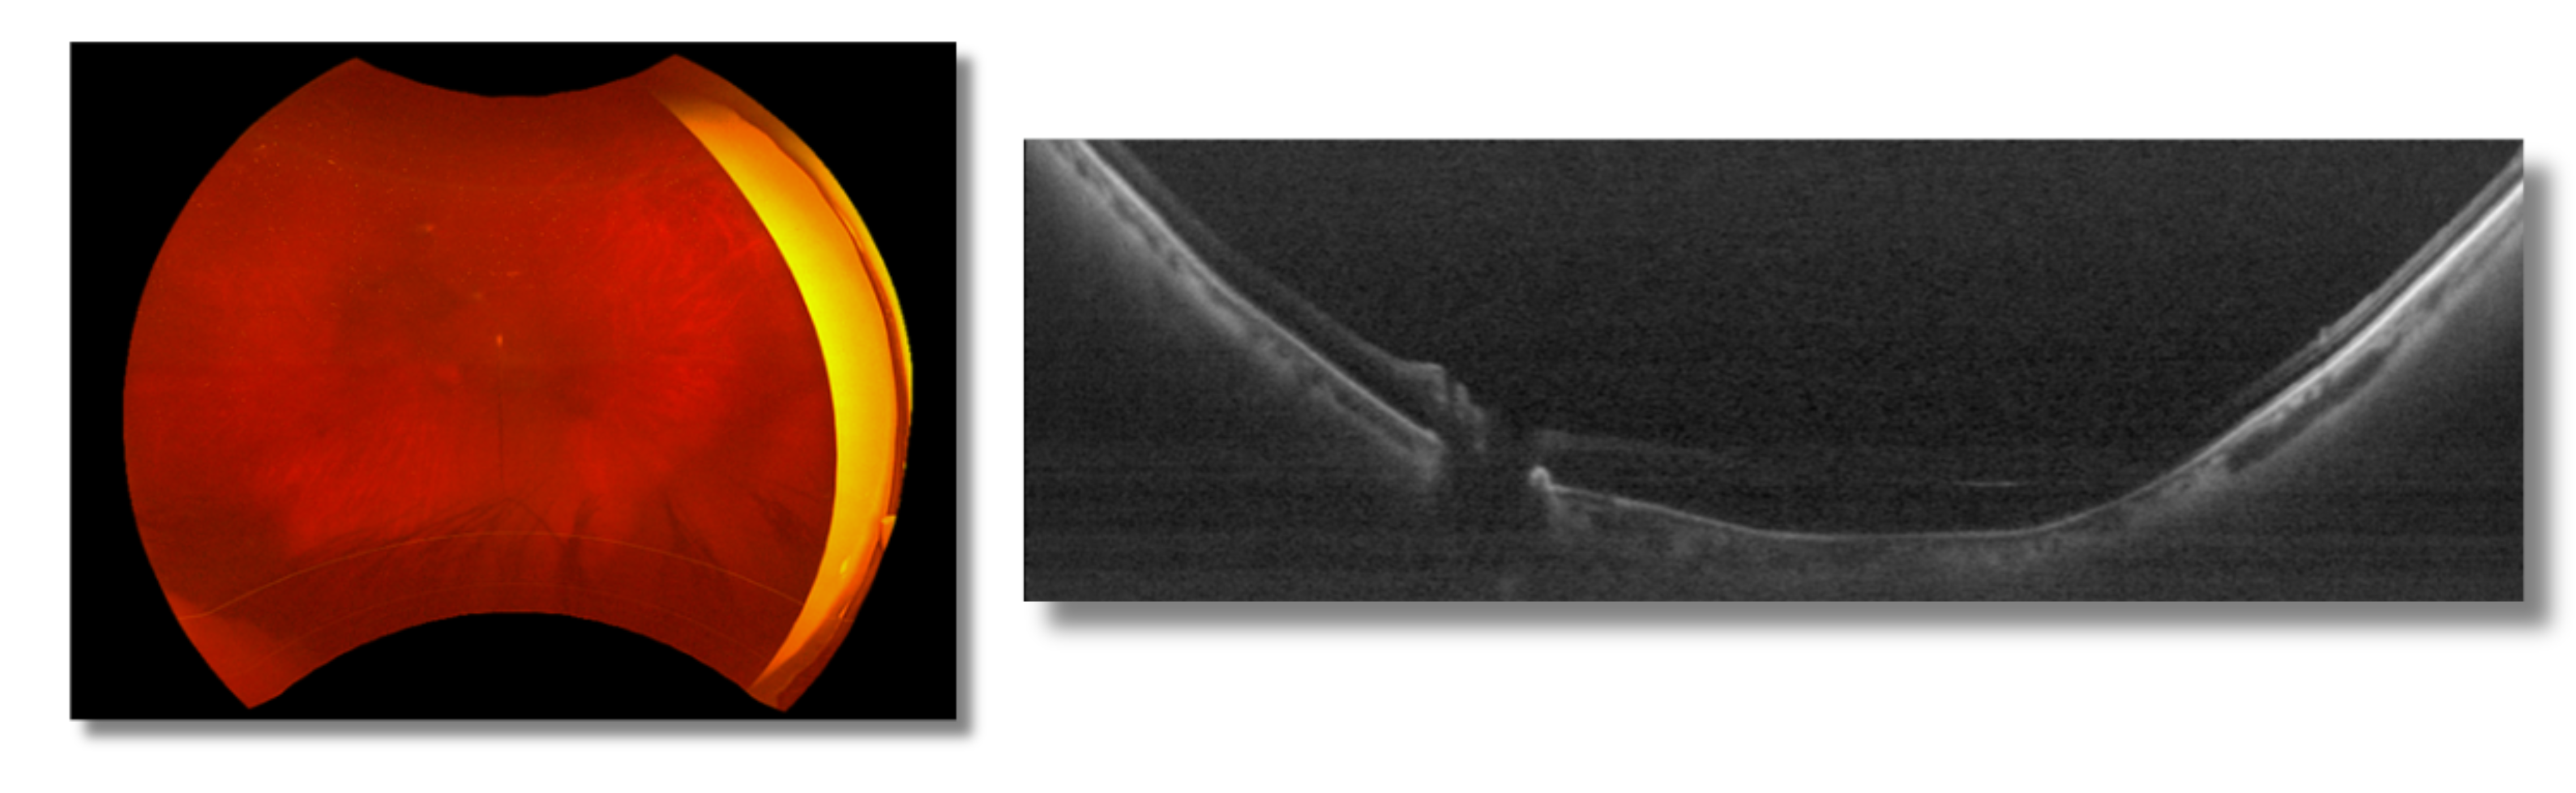

A 72-year-old male patient with dementia and a history of diabetes presented with significant visual impairment. The family reported challenges in daily care, including increased episodes of aggression and withdrawal—symptoms that had noticeably intensified in parallel with his declining vision. The patient had no light perception in the right eye and markedly reduced vision in the left. Best corrected visual acuity in the left eye was 0.2, improving slightly to 0.3 with pinhole testing. Examination revealed a dense, brunescent cataract in the left eye, with severely limited fundus visibility, as illustrated in the accompanying images (Figure 1). The family and patient were primarily concerned about whether cataract extraction could meaningfully improve his residual vision.

Figure 1: OCT & Fundus